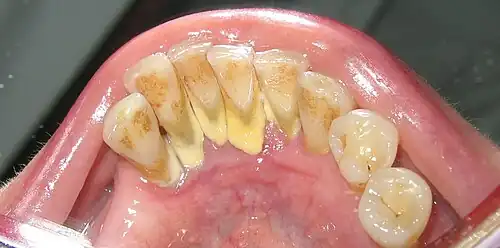

Mandibular anterior calculus

In dentistry, the term anterior teeth usually refers as a group to the incisors and canine teeth as distinguished from the posterior teeth, which are the premolars and molars. The distinction is one of anterior (front of the body) versus posterior (rear of the body). The distinction holds in both the upper jaw (maxilla) and lower jaw (mandible). As a rough guide, it can be said that the anterior teeth are tailored to biting (breaking the food into chewable chunks)[1] whereas the posterior teeth are tailored to chewing (comminuting the food into swallowable particles).